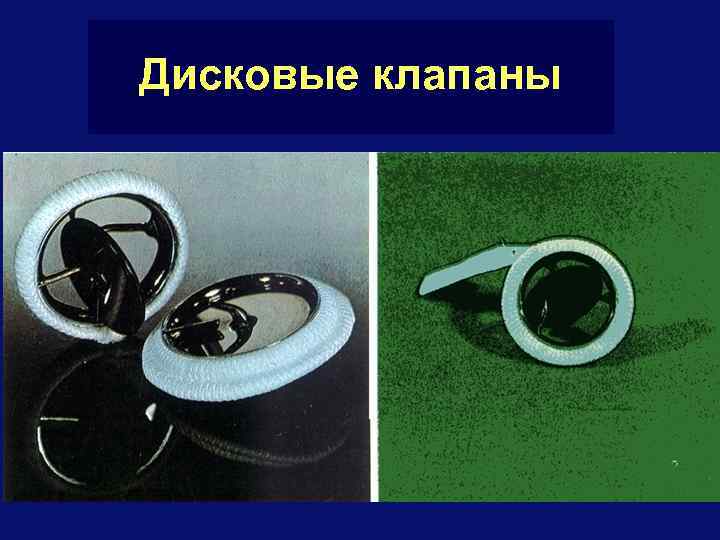

Клапаны сердца § Клапаны – искусственные и биологические § Искусственные более долговечны (20 лет), устойчивы к инфицированию, но требуют приема антикоагулянтов § Биологические не требуют приема антикоагулянтов, неустойчивы к инфицированию и наименее долговечны (не более 10 лет) § Из искусственных клапанов наиболее гемодинамически выгодные – дисковые (шарнирные), где шарнир в центре § Летальность при имплантации клапанов < 5 %

Дисковые клапаны